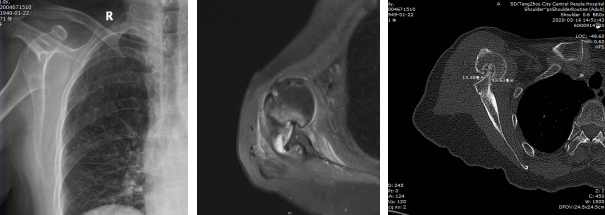

患者術(shù)前檢查:右肩關(guān)節(jié)前脫位,Hill-Sachs損傷,前盂唇損傷,二頭肌腱長頭腱脫位,右肩前脫位并嵌頓且存在骨缺損。

患者術(shù)后檢查:肩關(guān)節(jié)復(fù)位良好

患者老年女性,71歲,40余天前摔傷后出現(xiàn)右肩關(guān)節(jié)疼痛、活動受限,于我市某醫(yī)院就診,經(jīng)過保守治療無效,嚴(yán)重影響生活質(zhì)量。患者于3月13日來我院行右肩MRI檢查示:右肩關(guān)節(jié)脫位、右肩袖損傷、右肩諸肌損傷、右肩關(guān)節(jié)盂唇損傷、右肩關(guān)節(jié)積液,收入院。入院診斷為“1、右肩關(guān)節(jié)陳舊性前脫位 ;2、右肩關(guān)節(jié)Hill-Sachs 損傷;3、右肩關(guān)節(jié)Bankart損傷;4、右肩岡上肌腱損傷 ;5、右肩肱二頭肌長頭腱脫位?!?完善術(shù)前檢查后,為該患者在全麻下進(jìn)行“右肩關(guān)節(jié)鏡松解+肩關(guān)節(jié)脫位復(fù)位+岡上肌腱縫合固定+Bankart損傷修復(fù)+remplissage手術(shù)”,手術(shù)過程順利,術(shù)后恢復(fù)良好,患者肩關(guān)節(jié)癥狀明顯改善。